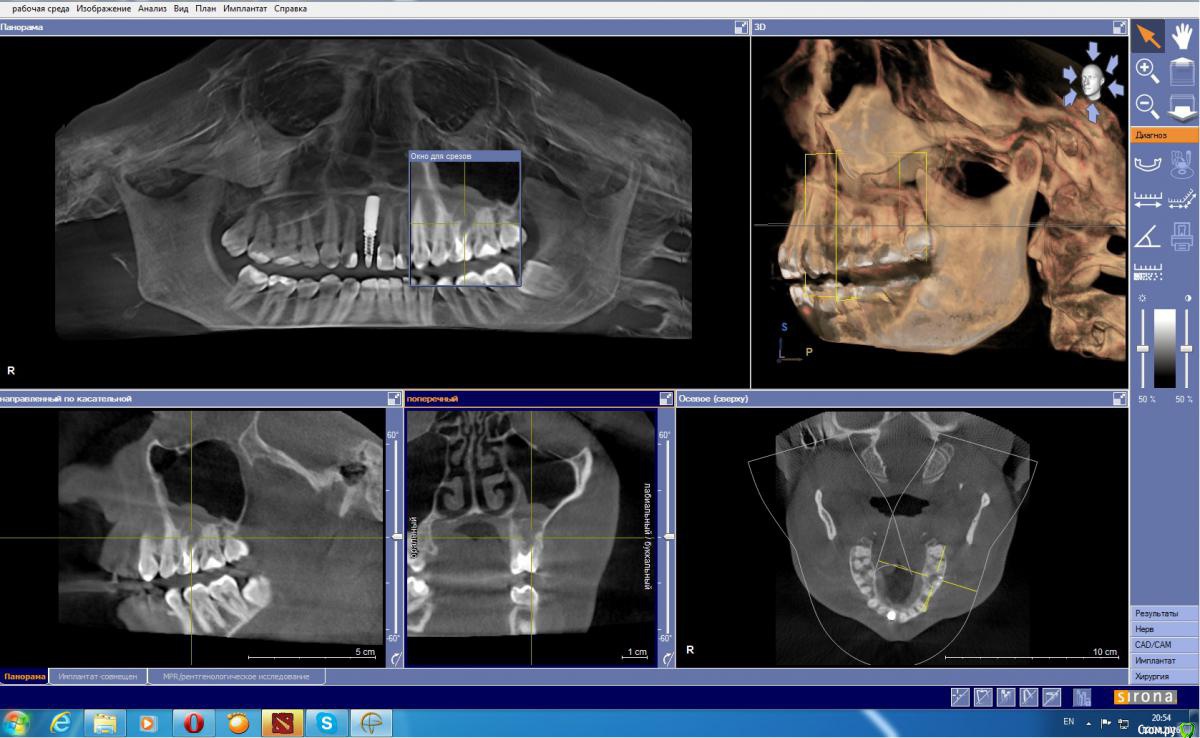

DmitrySH Опубликовано 21 апреля, 2016 Поделиться Опубликовано 21 апреля, 2016 Вы бы показали нам КТ и Все снимки которые есть, возможно мнение изменилось бы.По факту есть воспалительный процесс ( киста или нет это еще неизвестно) который затрагивает дно пазухи. И требуется устранение источника инфекции внутри зуба либо зуба целиком. Ссылка на комментарий

Fenya Опубликовано 21 апреля, 2016 Автор Поделиться Опубликовано 21 апреля, 2016 Вы бы показали нам КТ и Все снимки которые есть, возможно мнение изменилось бы.По факту есть воспалительный процесс ( киста или нет это еще неизвестно) который затрагивает дно пазухи. И требуется устранение источника инфекции внутри зуба либо зуба целиком. Такие скрины подходят или выложить все КТ? Если все, то подскажите, какие файлы выложить в файлообменник? Ссылка на комментарий

DmitrySH Опубликовано 21 апреля, 2016 Поделиться Опубликовано 21 апреля, 2016 Папку Data в ней должно быть много файлов с разрешением DCM все вместе заархивировать и выложить в файлообменник.Правда смогу посмотреть только завтра поздно вечером. Может кто-то еще посмотрит Ссылка на комментарий